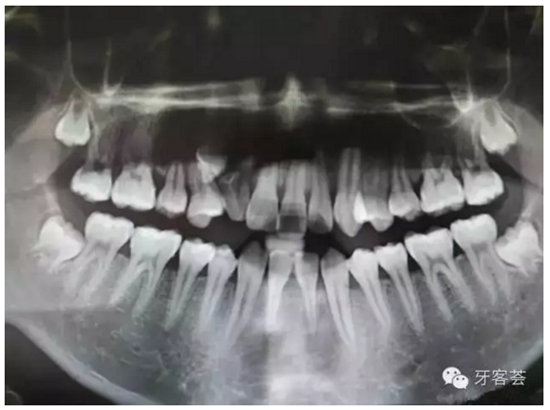

圖2:術(shù)前的全景片檢查:12牙根畸形。11、21根尖1/3橫折??上Э床磺甯鈾M折。